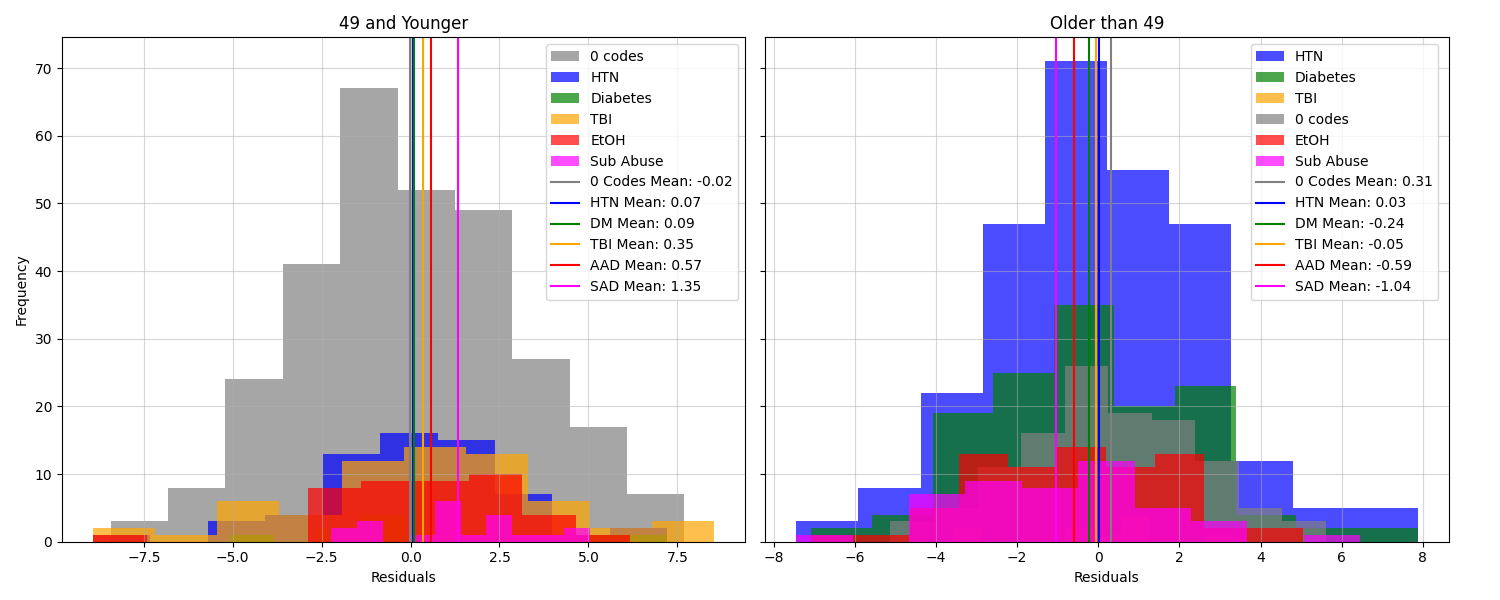

Statistical analysis corroborates this observation. A one-way ANOVA test of residuals grouped by the number of ICD codes did not yield statistically significant differences across the groups (). However, restricting the analysis to subjects older than 49 revealed significant differences (). Further exploration of this age-based split, as shown in Figure 8, highlights that residual means are positive (indicating a younger predicted brain age) for subjects aged 49 or younger, regardless of the specific ICD code. Notably, SAD exhibits the highest mean residual within this subgroup, though this result may be a statistical artifact due to the small sample size. Conversely, for subjects older than 49, residual means generally become negative, except for those with no associated ICD codes or those with HTN.

These findings suggest that while the five ICD codes exert a detectable influence on the residuals, their effects are secondary to the dominant influence of the patient’s actual age. Despite these limitations, the ability to detect these subtle associations in a dataset with inherent challenges and deviations from standard literature strengthens the case for BARBs as a promising area of future research.